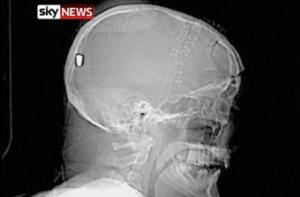

Однако рентгеновский снимок головы показал, что у Хесфорда в полости черепа находится инородный предмет. С помощью компьютерной томографии врачи установили, что этот предмет является пулей, и сообщили о находке полиции.

Изучившие снимки Хесфорда эксперты по баллистике пришли к выводу, что пуля, застрявшая в затылочной области, проникла в голову мужчины через глаз. У него самого воспоминаний о происшедшем не сохранилось.

_Снимок головы Хесфорда. Кадр Sky News_